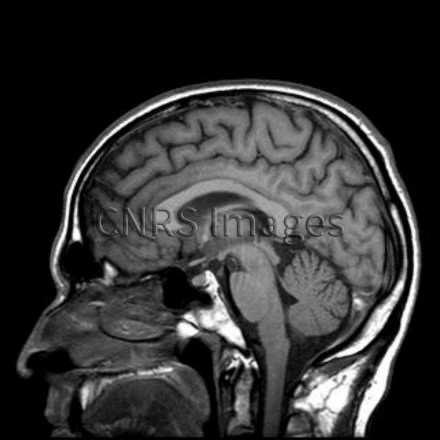

Coucou, alors un plan sagittal, ça veut dire que sur un plan vertical, on séparé un objet en deux parties égales, en une partie droite et une partie gauche. Et que la coupe va d'avant en arrière. Si on sépare en deux parties inégales alors ça sera un plan para-sagittal.

Par exemple, lors d'un IRM on fait des coupes sagittales du cerveau, du devant de la tête jusqu'à l'arrière.

Quand on dit que quelque chose est placé dans un plan sagittal c'est qu'il est en direction de ce plan d'avant en arrière ou dans l'alignement qui sépare la gauche et la droite.

Quand un objet est sur le plan sagittal c'est qu'il est au milieu, qu'il sépare la gauche et la droite, par exemple dans le plan sagittal on a le nez, le nombril, la colonne vertébrale.

image.png.e6e67dbe96e55c4ec594ab3278c46701.png